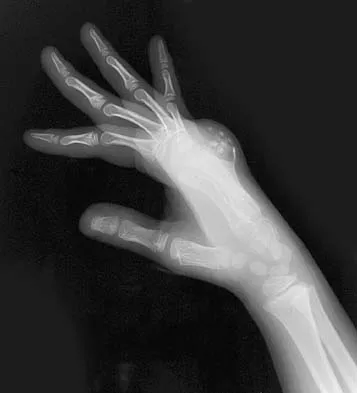

The arrow in Figure 39 is pointing to which of the following ligaments?

Explanation

The lunotriquetral interosseous ligament stabilizes the lunotriquetral joint. The scapholunate interosseous ligament stabilizes the scapholunate joint. The ulnolunate ligament originates from the base of the ulnar styloid and inserts in the lunate. The ulnotriquetral ligament originates from the base of the ulnar styloid and inserts on the triquetrum. The ulnolunate and the ulnotriquetral ligaments are important stabilizers to the ulnar side of the wrist. The short radiolunate ligament originates on the volar ulnar margin of the distal radius and inserts in the ulnar margin of the lunate. Berger RA: Ligament anatomy, in Cooney WP, Linscheid RL, Dobyns JH (eds): The Wrist, Diagnosis and Operative Management. St Louis, MO, Mosby, 1998, pp 73-105.